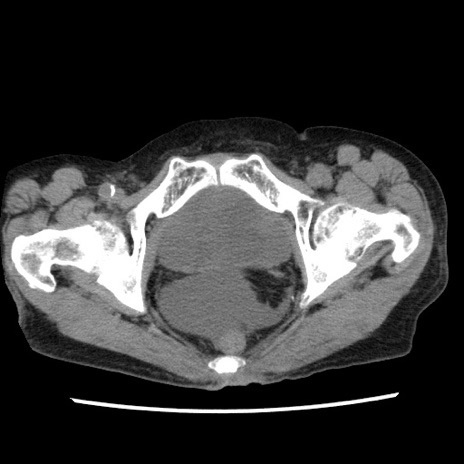

症例1(横断像)

症例

【症例】80歳代女性

【主訴】腹痛

【現病歴】8時間前から腹痛あり来院。

【既往歴】糖尿病、脂質異常症、子宮体癌にて子宮全摘術

【身体所見】意識清明・会話良好だが腹痛で苦悶様、全腹部にわたって反跳痛と圧痛あり

【データ】WBC 13600、CRP 0.14、LDH 224、CK 90